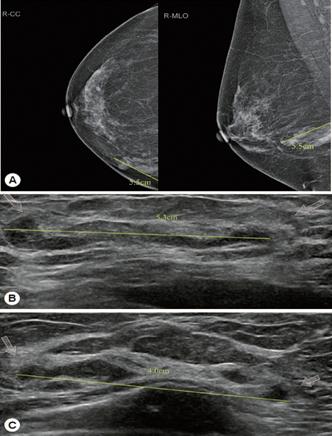

Bệnh ấu trùng sán nhái ở sinh dục tiết niệu (Urogenital sparganosis)

Trong bệnh sán nhái sinh dục, các nốt dưới da xuất hiện tại vùng háng, âm hộ hay bìu giống như khối u.

| Hình 13.Tổn thương sán nhái Spirometra spp. ở bìu và một bên của vú |